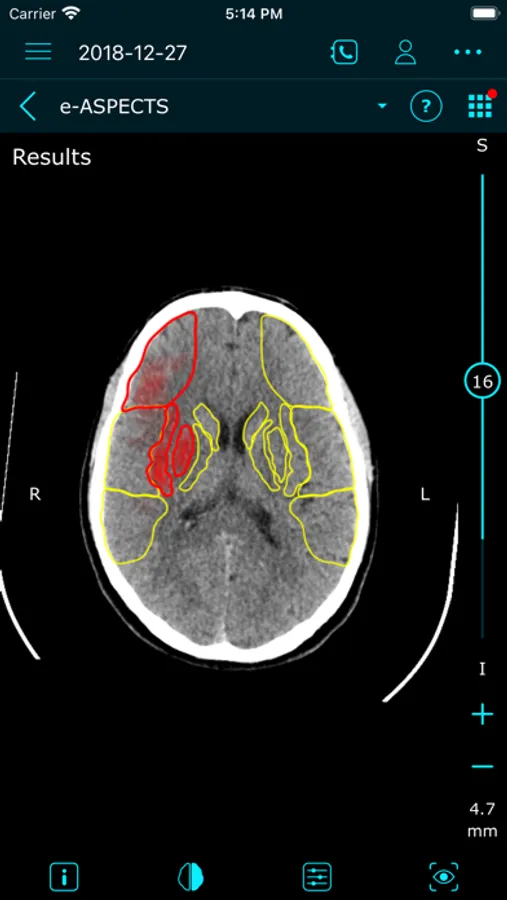

e-Stroke consists of three modules (e-ASPECTS*, e-CTA*, and e-CTP*), supporting the full range of stroke imaging needs, from simple NCCT scans, to more advanced CT Perfusion assessments.